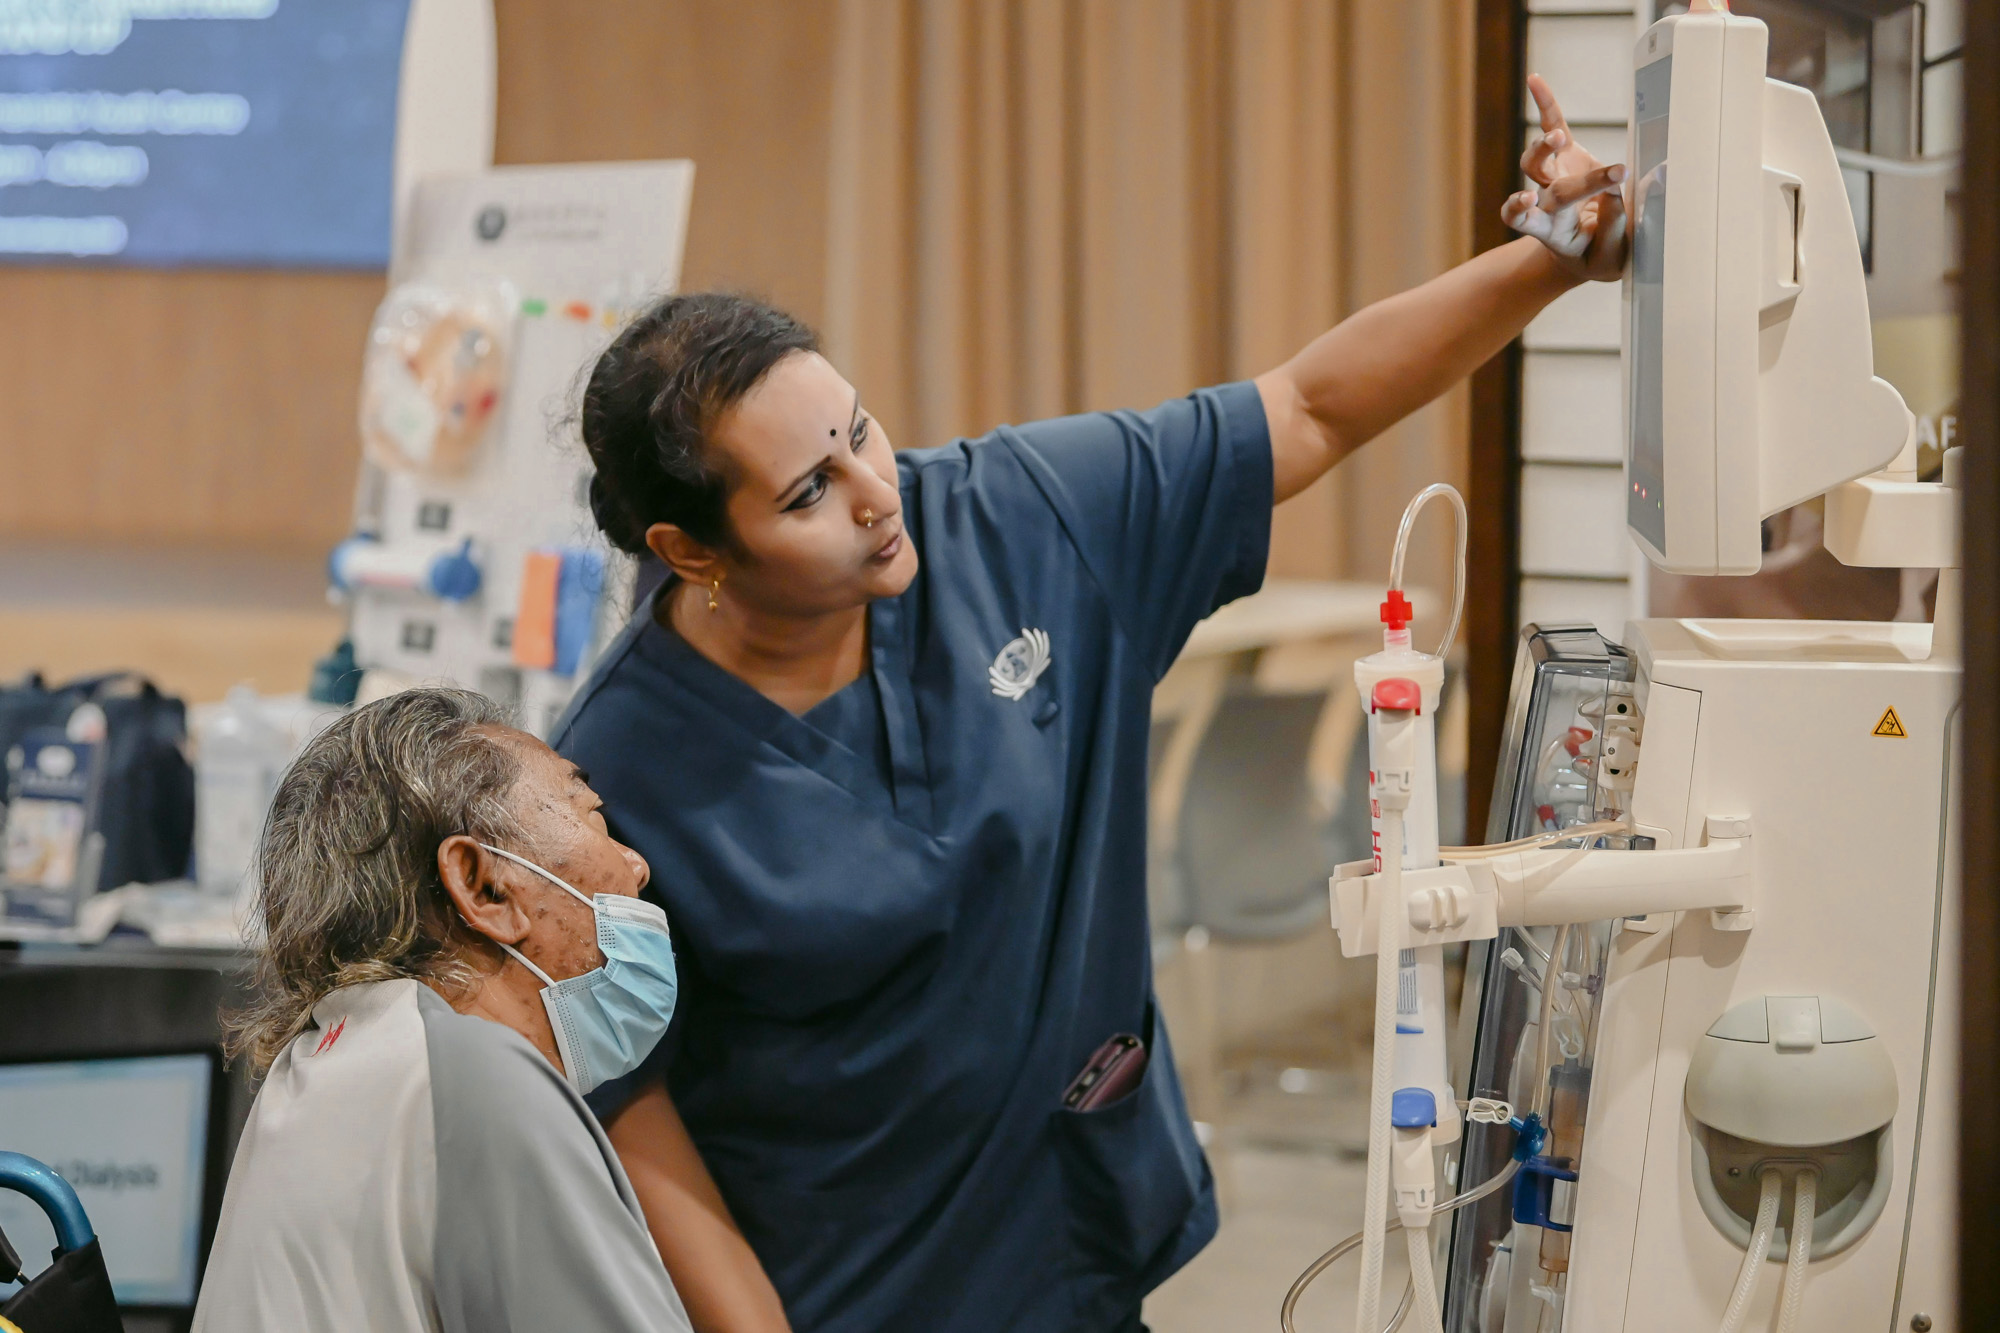

慈济洗肾中心职工Sudha Aravindar耐心地向肾友讲解洗肾机功能。摄/ 蔡佑良

此外,大会也向有关单位借一台洗肾机放在现场展示。慈济洗肾中心能顺利运营,少不了医护人员与值班志工的付出与守护。经验丰富的医护人员Sudha Aravindar在几个月前加入慈济洗肾中心。尽管加入时间不长,她已观察到该中心的营运方式与其他医疗机构不同。

她举例,慈济洗肾中心的营运时间从早上7时至晚上11时,已超出一般营运时间,只为了能服务到有上班的肾友。尽管营运时间较长,但为确保医护人员能获得充分休息,中心将轮班分成三个时段。“这样我们才有精神和力量去更好地关怀他人。”Sudha Aravindar说道。